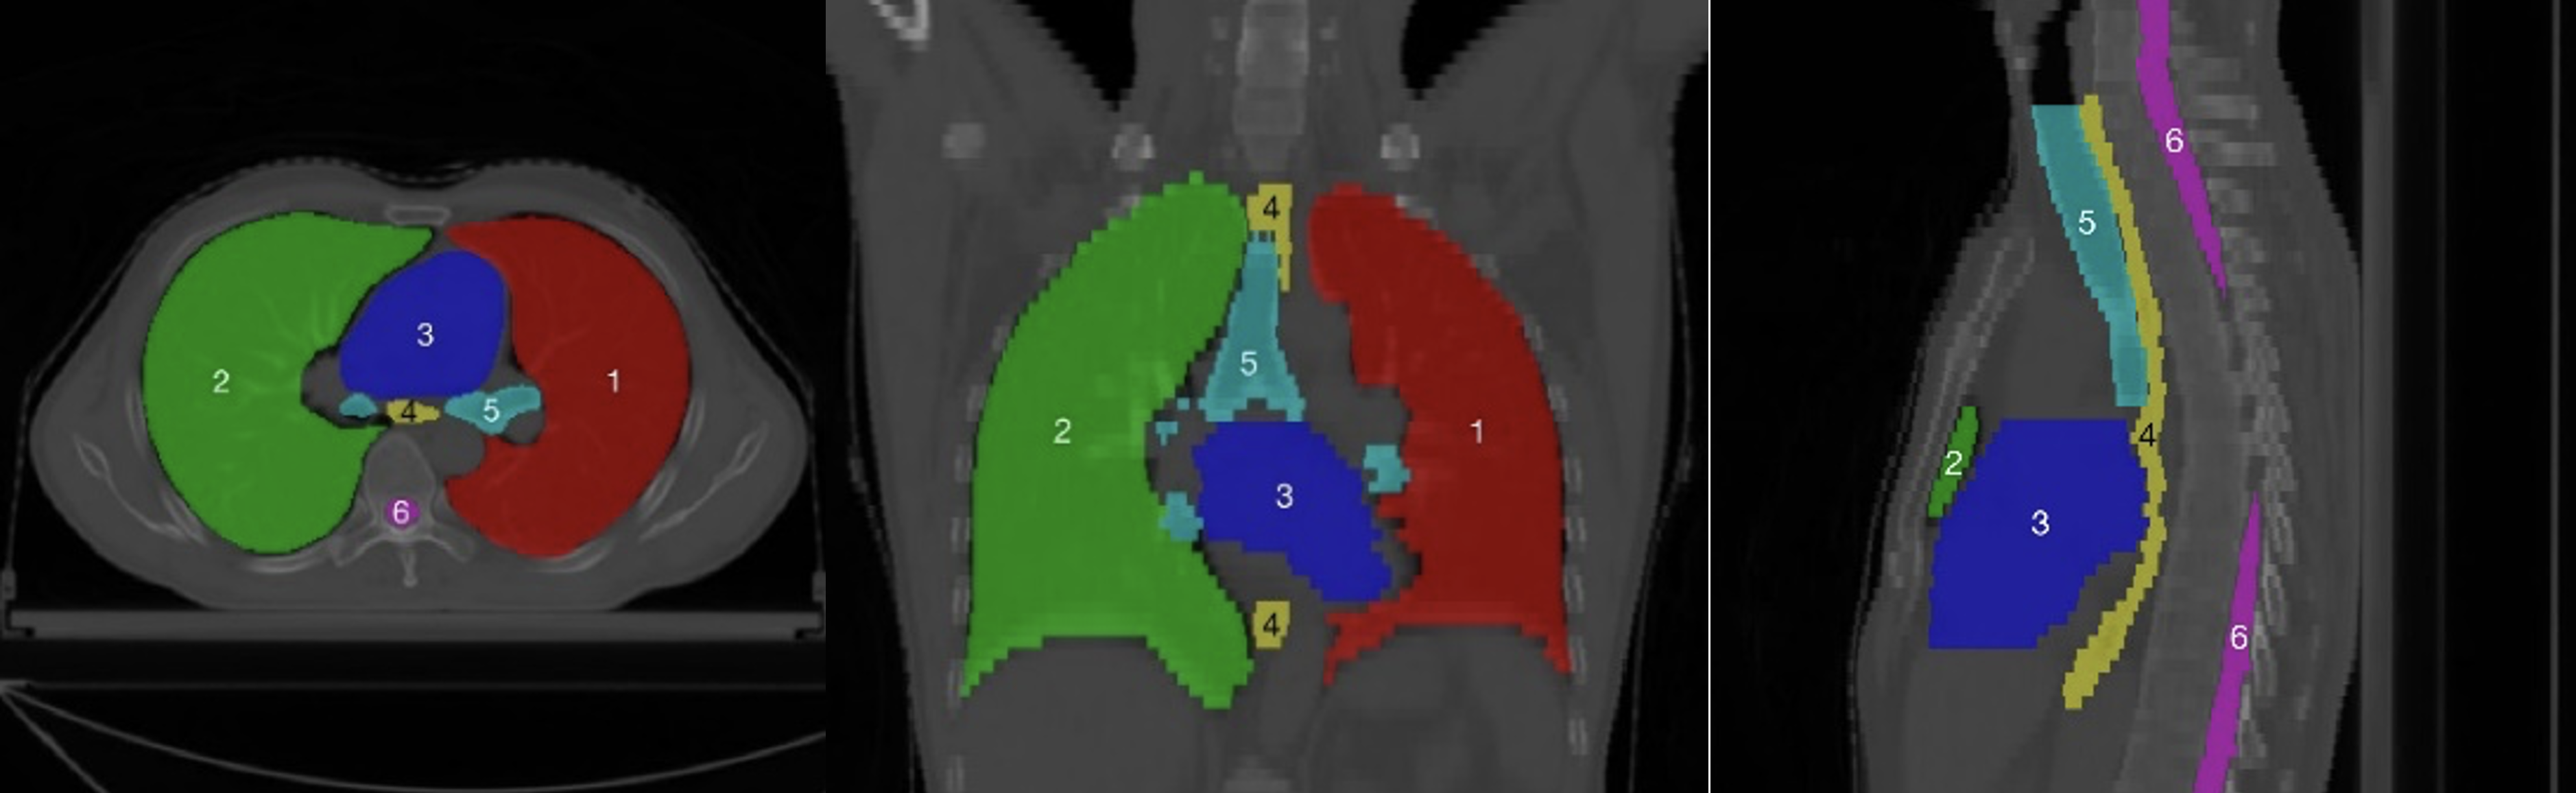

Using data-driven feature extraction approach and end-to-end training, the methods based on deep learning (DL) have been widely studied in the fields of image classification [21], object detection [22] and image segmentation [23, 24], image fusion [25], image registration [26], etc. The segmentation method based on deep learning has become a mainstream method in the field of medical image processing. However, there are two main difficulties in multi-organ deep learning segmentation tasks. First, as shown in the head and neck in Fig. 1, the abdomen in Fig. 2, the chest in Fig. 3, and the statistics of the multi-organ size in each part in Fig. 4, there are very large differences between the organs sizes, and the serious imbalances of different organs sizes will lead to a poor segmentation performance of the trained segmentation network for small organs. Second, due to the imaging principle of CT technology and the complex anatomical structure of the human body, the contrast between organs and their surrounding tissues is often low, which leads to the inaccurate segmentation of organ boundaries by segmentation networks. Therefore, it has become a new hot research topic to develop deep multi-organ segmentation methods that can accurately segment small and large organs at the same time.

The current multi-organ segmentation method is more effective in solving the segmentation of large organs and organs with standard contours, such as the brainstem and mandible in the head and neck; the left and right lungs and heart in the chest; and the liver, spleen, and stomach in the abdomen. Moreover, the DSC of various methods can basically reach 0.8 or higher, while for small organs, such as the optical chiasm in the head and neck (see Fig. 1(8)), the left and right optic nerves (see Fig. 1(6 and 7)), the DSC can only reach about 0.7; irregular organs such as the pancreas in the abdomen (Fig. 2(4)), and long striped organs such as the spinal cord (Fig. 2(6)), the segmentation results are also not very satisfactory. The future research direction is to enhance the segmentation accuracy of these types of organs using more advanced automatic segmentation frameworks.